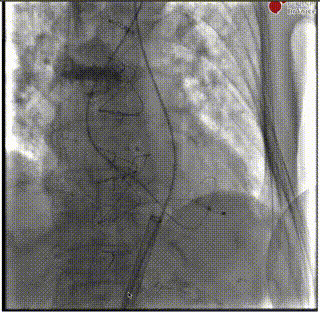

导丝跨瓣

交换猪尾

输送系统过弓

释放初期预释放

释放到50%回收

快速起搏下释放到80%

释放前造影确定位置和深度